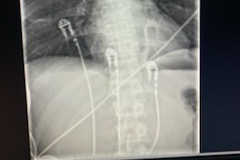

He reached into his pocket to call 911 only to see no service available. He knew that the area that he was in would have been an air-transport via helicopter. At that moment fight or flight set in and he chose fight. He somehow miraculously got up from the dirt, grabbed the bike to use it as a walker and walked out to find service at a better location for fire fighters/ ambulance “The walk of hell” he calls it.... Once he reached an upward slope where he couldn’t pull the weight of the bike, He ditched it and made way up the slope to the grassy turnoff on the side of a road. He sat in the grass yelling for help.. he reached into his pocket one more time and called 911. From there, Brock was transported safely to the hospital by the ambulance team. He has in undr gone spinal surgury. They had to fuse his neck and back to stabilize his spine. the artery in his neck was severed from the blunt force inpacked. He has a very bad concusion. His lung was punctured and was bleeding internaly. Lucky to be alive and able to walk. Brock will continue to need surguries and a lot of physical therapy. Anything helps, let's please help Brock get the surgery and treatment to heal.

- Multiple fractures in spine

-Severed artery in his neck

For Surgery :

-C2- T5 fusion

-T11 T12 operation if needed

-Revision surgery in 6 months